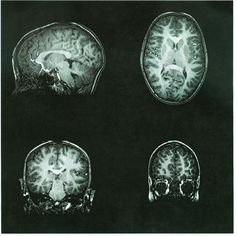

铅中毒会影响孩子的认知发育。(图片来源:Child brainscan image via www.shutterstock.com.)

在大脑中,铅可以破坏神经元细胞内线粒体的功能,从而使得细胞不能正常运转。它也可以影响神经递质(神经元间通信的物质)的传递并改变大脑中血管的结构。综上所述,这种损伤可能会导致智商下降、学习障碍、生长减缓、多动症和缺乏对冲动的控制力,甚至是听力障碍。这就是为什么大家特别关注儿童铅中毒的问题。